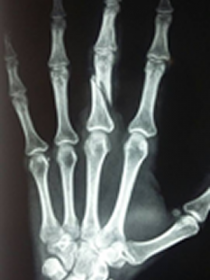

Segundo o secretário municipal de saúde, Manoelito Rodrigues, a médica teve o dedo médio fraturado e deve passar por uma cirurgia.